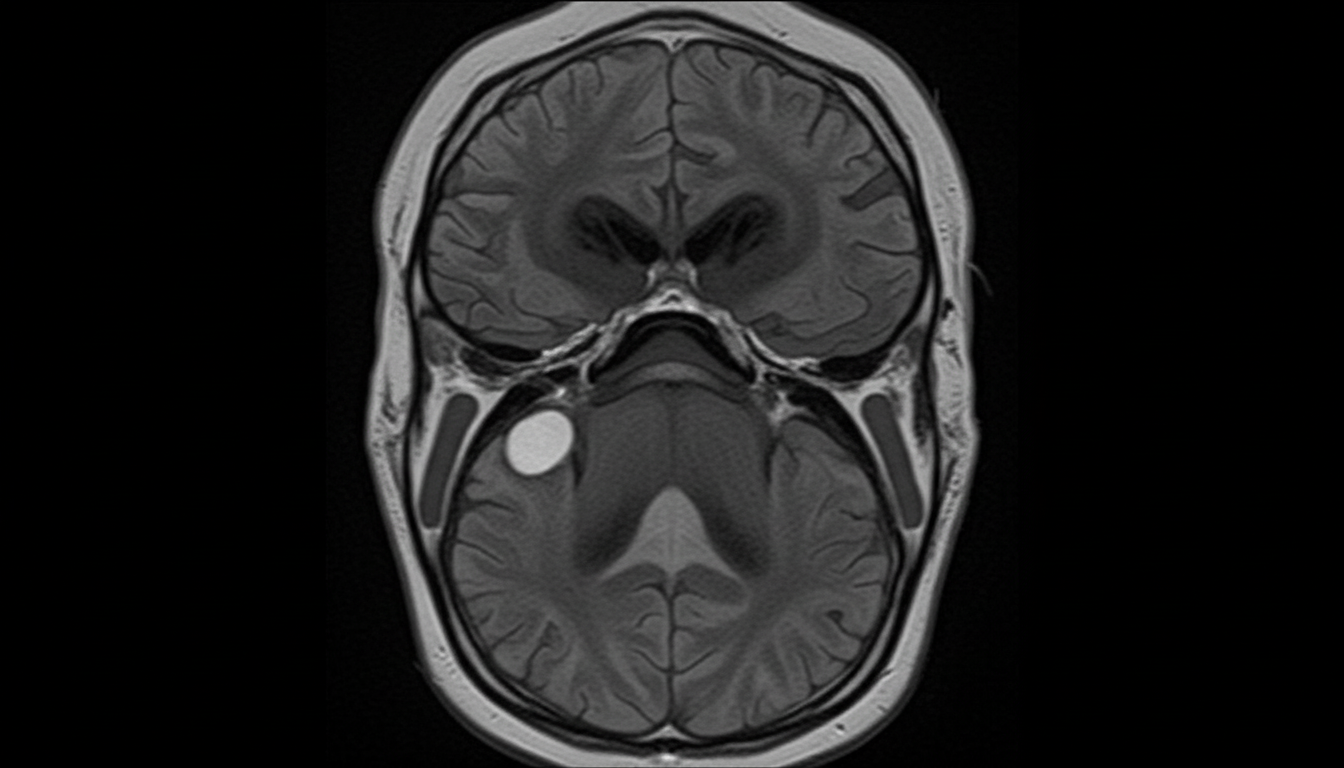

A 50-year-old male presented with progressive unilateral sensorineural hearing loss associated with tinnitus for 2 years. He reported marked difficulty in understanding speech, disproportionate to the pure-tone hearing loss. The patient also complained of reduced corneal sensitivity, numbness, and paresthesia of the face, along with hypoesthesia of the posterior meatal wall. Otoscopy revealed a sensorineural type of hearing loss with a poor speech discrimination score, absence of recruitment phenomena, and an SISI score of 0-20%. Based on imaging findings (CEMRI), which of the following structures is LEAST likely to be involved in the most common site for this pathology?

Explanation: **Explanation:** Vestibular Schwannoma (Acoustic Neuroma) is a benign tumor of the 8th cranial nerve. It is a classic example of a **retrocochlear lesion**. Understanding the distinction between cochlear (sensory) and retrocochlear (neural) pathology is key to answering this question. **1. Why Option D is Correct:** The **Rollover Phenomenon** is a hallmark of retrocochlear lesions. In speech audiometry, as the intensity of sound increases, the speech discrimination score (SDS) initially improves but then significantly **decreases** (rolls over) at higher intensities. This happens because the damaged nerve fibers cannot handle the increased neural load, leading to "neural fatigue." **2. Why the Other Options are Incorrect:** * **Options B & C:** **Recruitment** and a **High SISI score** (Short Increment Sensitivity Index >70%) are characteristic features of **Cochlear lesions** (e.g., Meniere’s disease). In retrocochlear lesions like Vestibular Schwannoma, recruitment is absent (Decruitment may be seen), and the SISI score is low (0-20%). * **Option A:** A **Diverging ABLB Laddergram** (Alternate Binomial Loudness Balance) indicates recruitment (cochlear). In retrocochlear lesions, the laddergram would show no recruitment or a **converging** pattern only if it were a different pathology; however, the classic finding for Schwannoma is the absence of recruitment. **Clinical Pearls for NEET-PG:** * **Earliest symptom:** Progressive unilateral sensorineural hearing loss (SNHL) and tinnitus. * **Earliest sign:** Loss of corneal reflex (due to CN V involvement). * **Gold Standard Investigation:** Gadolinium-enhanced MRI (shows "Ice-cream cone" appearance in the CP angle). * **Audiological profile:** Poor speech discrimination out of proportion to pure tone loss, Tone Decay >30 dB, and absent stapedial reflex.

Explanation: ***Posterior inferior cerebellar artery*** - **PICA** originates from the **vertebral artery** and supplies the **lateral medulla** and **inferior cerebellum**, remaining distant from the **cerebellopontine angle (CPA)** and **internal auditory canal (IAC)**. - In **acoustic neuroma** (vestibular schwannoma), PICA is anatomically separated from the tumor location and is **rarely compressed** or displaced by CPA masses. *Facial nerve* - The **facial nerve (CN VII)** runs adjacent to the **vestibulocochlear nerve (CN VIII)** in the **IAC** and **CPA**, making it commonly affected in acoustic neuromas. - Facial involvement causes **reduced corneal sensitivity** and **facial numbness/paresthesia**, as described by **Hitselberger's sign** in this case. *Flocculus of the cerebellum* - The **flocculus** is located in the **CPA** and can be compressed by expanding acoustic neuromas, causing **vestibular dysfunction** and **balance issues**. - Its proximity to the **IAC** makes it susceptible to displacement by **CPA masses**, contributing to the patient's symptoms. *Anterior inferior cerebellar artery* - **AICA** courses through the **CPA** and **IAC**, making it commonly displaced or compressed by acoustic neuromas in this region. - AICA involvement can contribute to **cochlear ischemia** and worsen **sensorineural hearing loss** with poor **speech discrimination scores**.